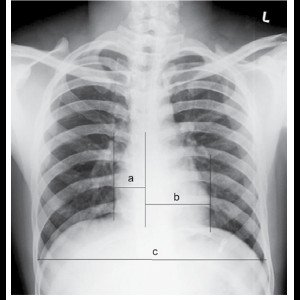

Role of Radiography in Congenital Heart Diseases

Role of Radiography in Congenital Heart Diseases

Role of Radiography in Congenital Heart Diseases

Role of Radiography in Congenital Heart Diseases